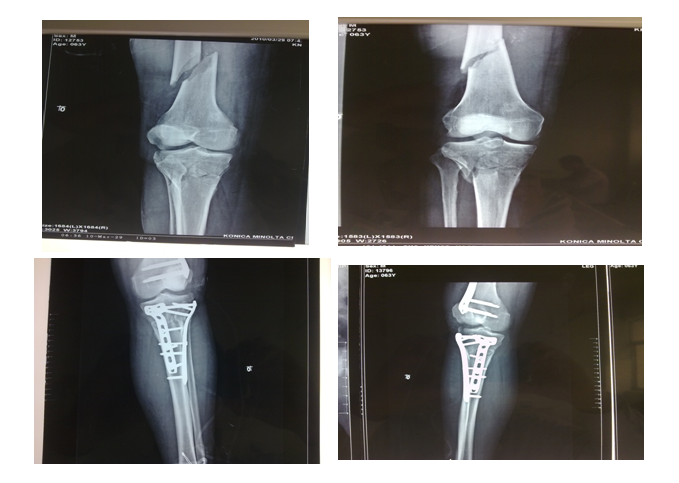

浮膝损伤内固定治疗前后

Pilon骨折内固定+外固定治疗